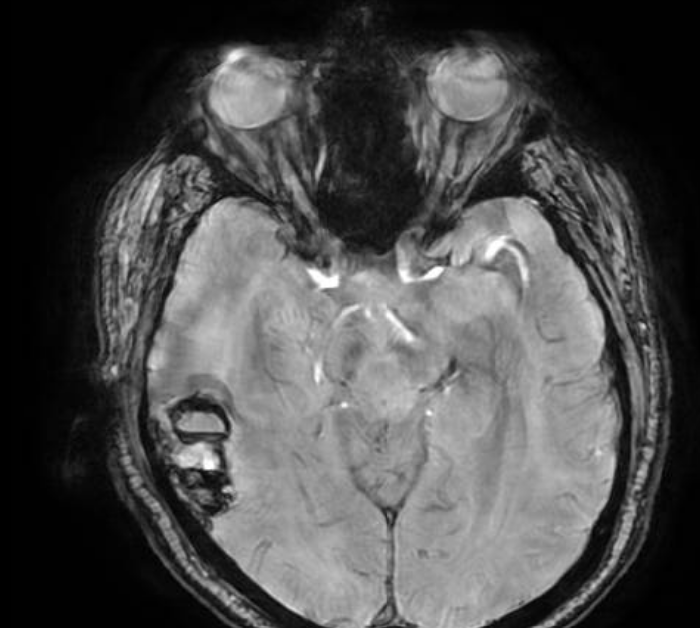

In 2013, after months of severe headaches, doctors discovered a rare and aggressive cancer—stage 4 neuroesthesioblastoma, a tumor extending from his nose to his brain.

By the time doctors found the tumor, it had already grown significantly and is now pressing on critical areas of his brain.

He needs urgent brain surgery to survive.

Without this surgery, doctors have told us he may have only about six months to live.